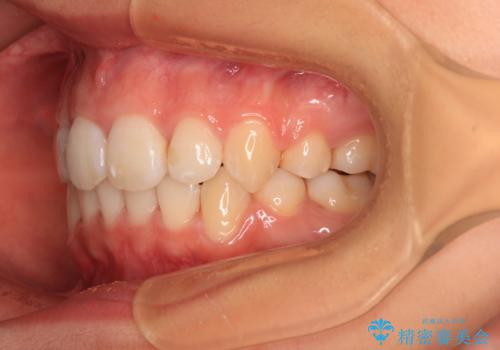

補助装置を併用したおかげでスムーズに奥歯の咬み合わせを改善することができ、我々も予想できないくらい理想的な仕上がりにすることができました。